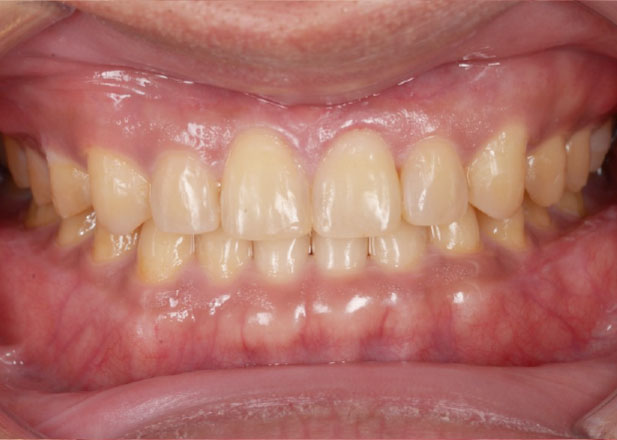

すきっ歯を治したい

正中離開(すきっ歯)は年齢とともに進行しやすいです。進行をとめるためには見た目の改善だけではなく、全体のかみ合わせを整えることが重要です。

口腔内写真

治療後

主訴 正中離開(すきっ歯)を治したい。

治療期間 1年